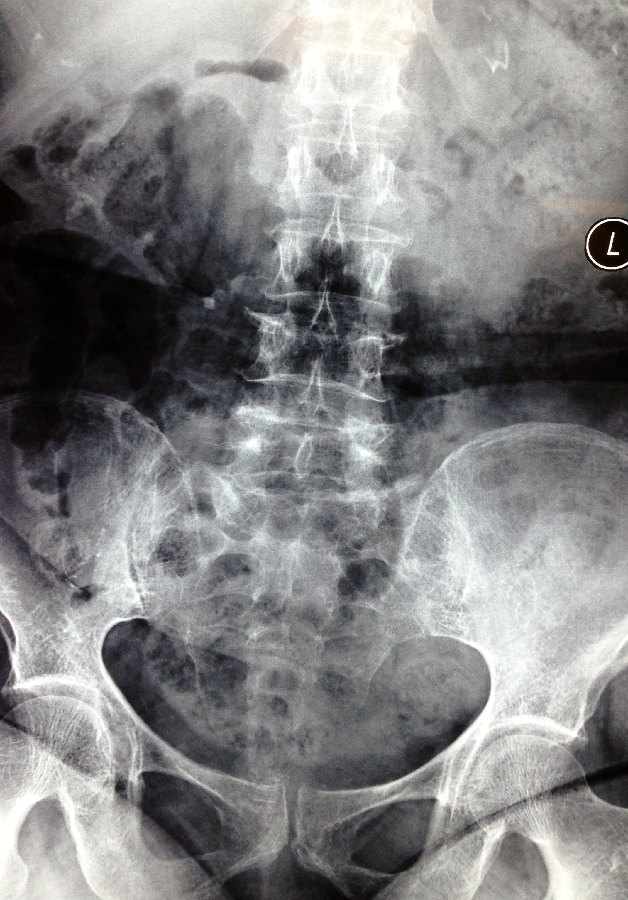

X-rays of her lumbar spine showed a possible fracture of the L4 vertebra.